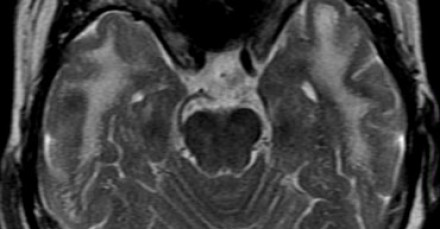

多發(fā)斑塊狀病灶的鑒別診斷

圖片一

在上圖中,是各種多發(fā)性點狀和斑塊狀白質(zhì)病灶圖像,我們對其中部分病例進行詳細討論。需要說明的是,以下鑒別診斷中提到的疾病與上圖中的圖像并不完全重合。

交界區(qū)腦梗死

MRI成像病灶要點:一般來說,這些病灶僅位于一個腦半球,要么位于深層白質(zhì)與灰質(zhì)的分水嶺區(qū)域(watershed area),要么位于周圍的分水嶺區(qū)域。在上圖中,病灶位于深層的分水嶺區(qū)域。

急性播散性腦脊髓炎(ADEM)

MRI成像病灶要點:在感染或接種疫苗后10-14天,多個局灶性病灶出現(xiàn)在腦白質(zhì)和基底節(jié)。與MS一樣,ADEM病變可累及脊髓、U形纖維以及胼胝體,有時可出現(xiàn)增強病灶。與MS所不同的是,ADEM的病灶通常更大,且好發(fā)于青年人,病程是單相的。

萊姆病

病灶大小約為2-3毫米,與MS的病灶相似,但患者會有皮疹和其他流感樣疾病。脊髓呈現(xiàn)高信號,CN7(神經(jīng)根入腦干區(qū))信號增強。

肉樣瘤

肉樣瘤的病灶分布與MS非常相似。

進行性多灶性白質(zhì)腦病(PML)

PML是一種由JC病毒感染引起的脫髓鞘性疾病,常見于免疫抑制患者。

MRI成像病灶要點:白質(zhì)損傷病灶在U形纖維的間隙占位,不增強,與HIV或CMV不同。

PML的病灶可在單側(cè)出現(xiàn),但更常見的是呈雙層、不對稱性分布。

血管周圍間隙(Virchow Robin spaces)

MRI成像病灶要點:T2加權(quán)成像明亮,F(xiàn)LAIR成像黑暗。

小血管性疾病

白質(zhì)損傷病灶位于深層白質(zhì)區(qū)域,不位于胼胝體、腦室旁或皮層旁。